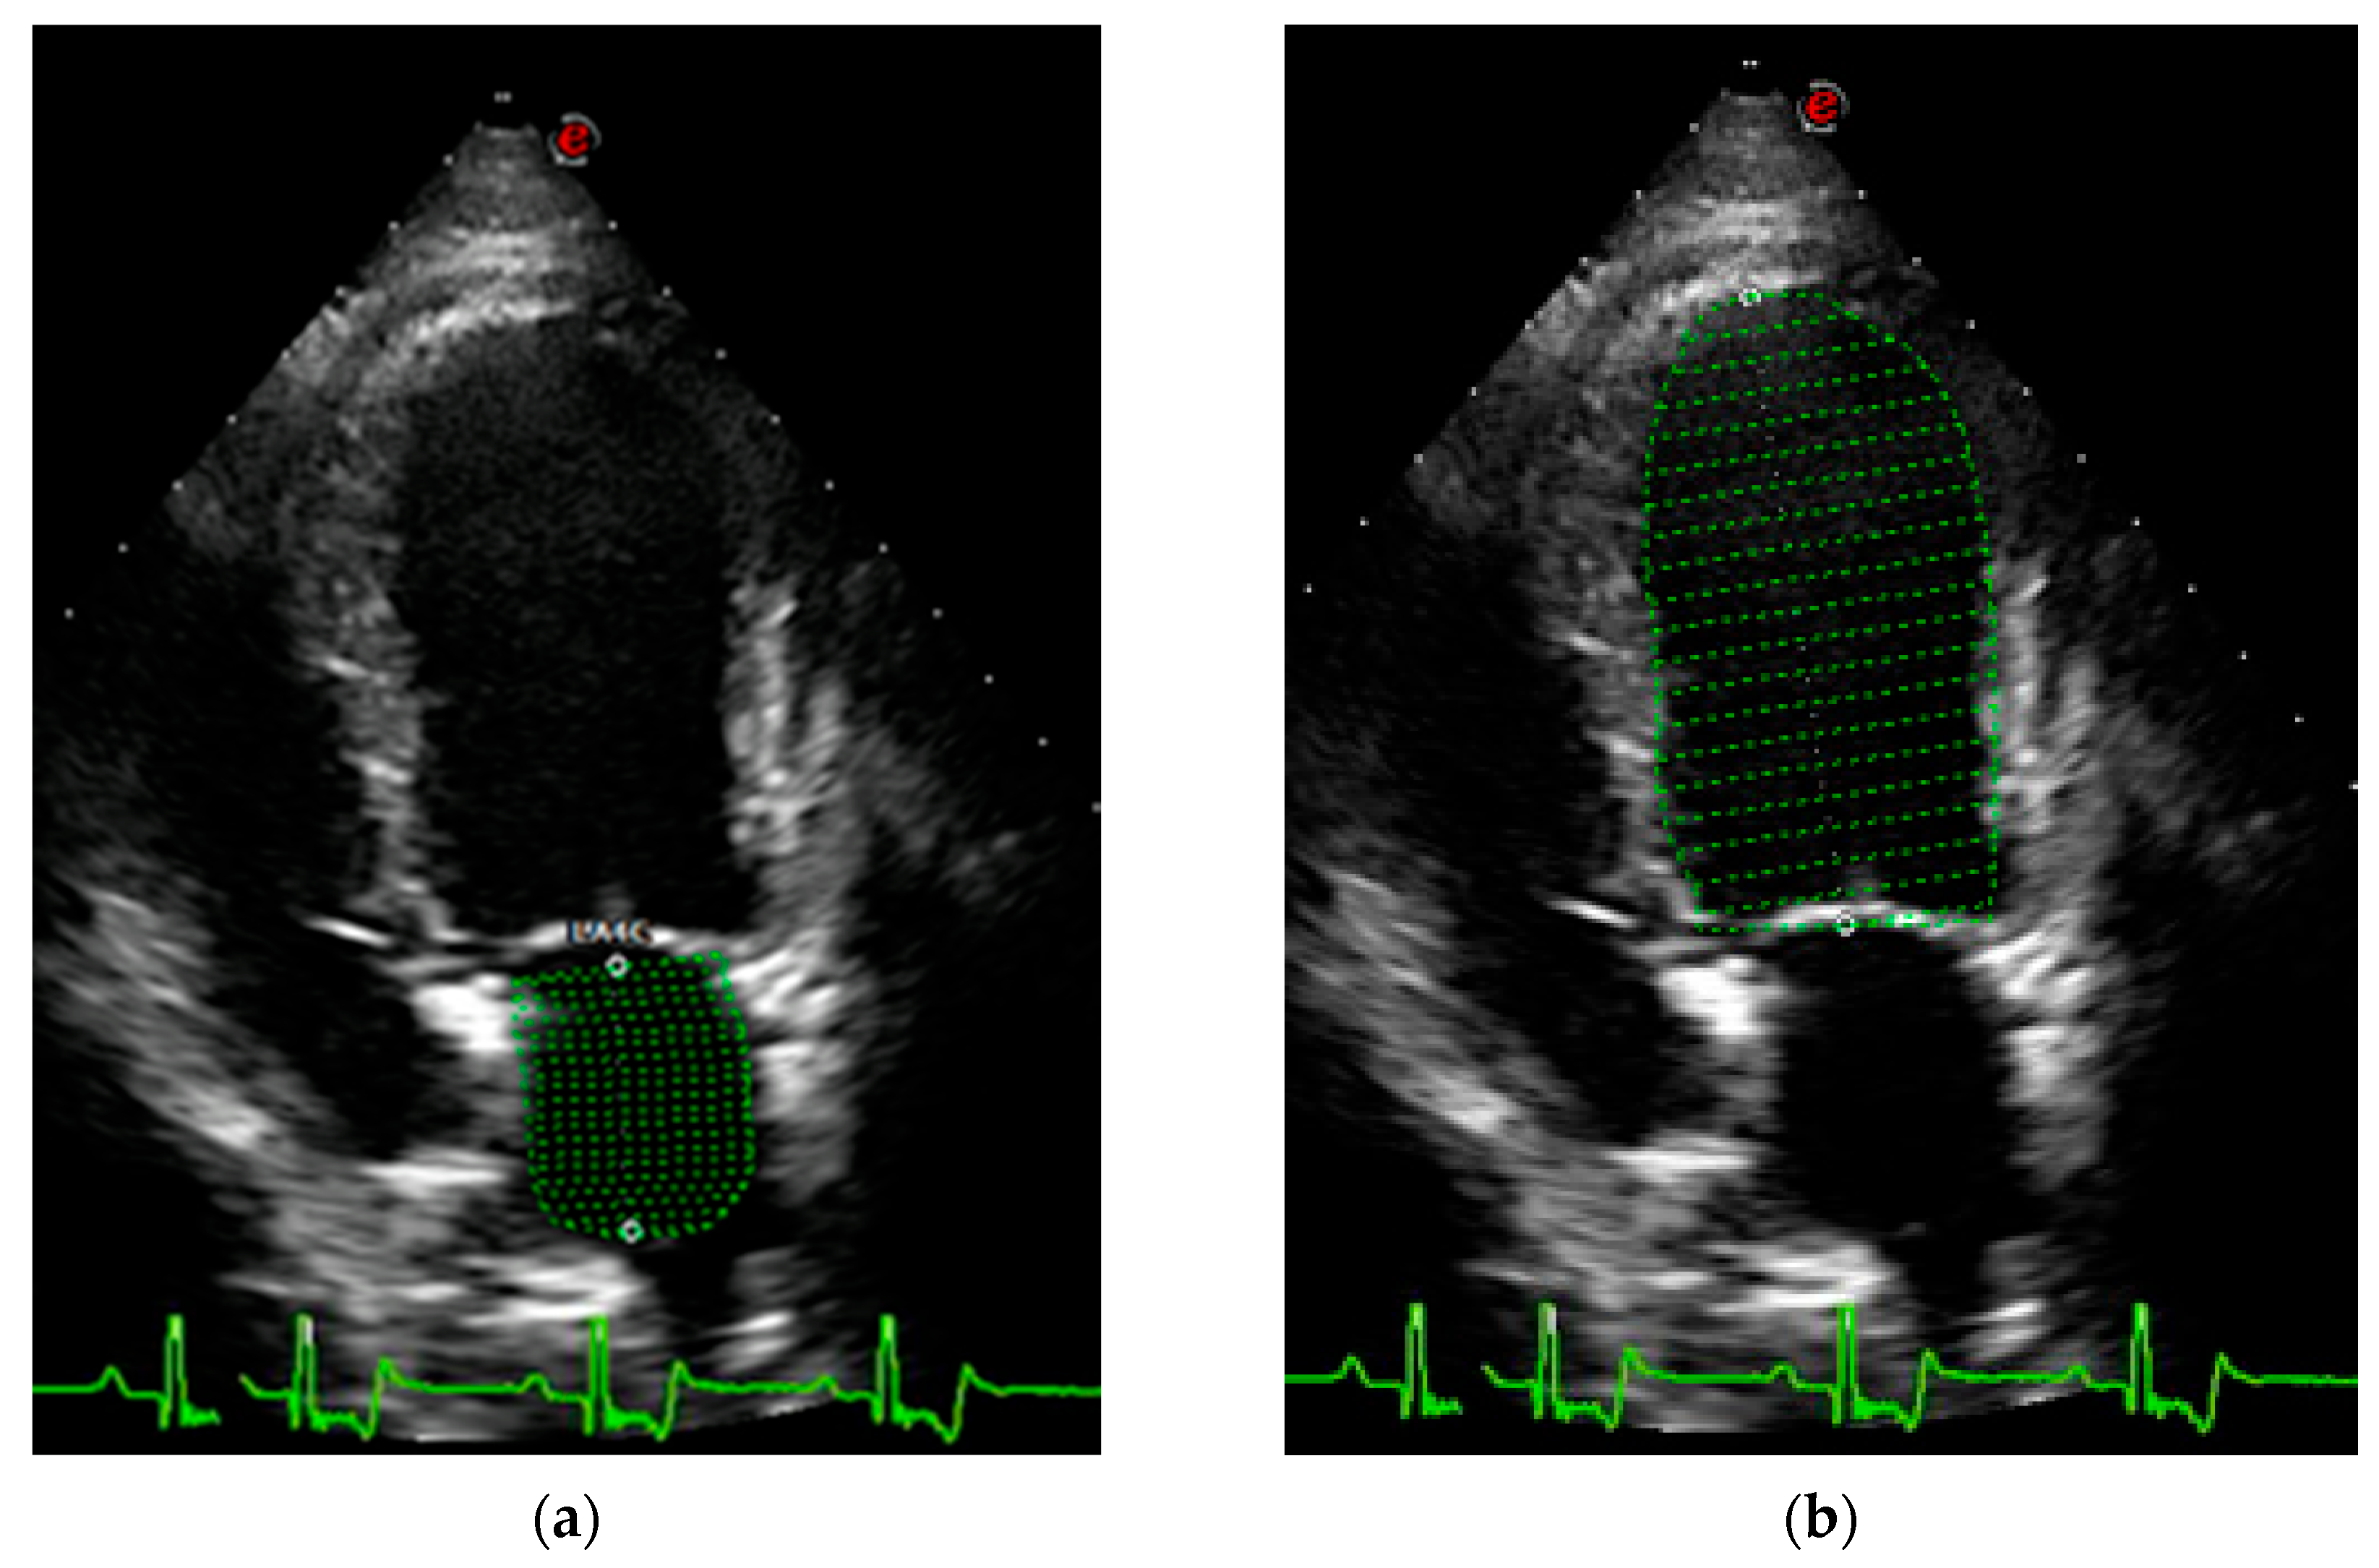

- LACi-ED (%) = LA end-diastolic volume (LAEDV)/LV end-diastolic volume (LVEDV) × 100.

- LACi-ES (%) = LA end-systolic volume (LAESV)/LV end-systolic volume (LVESV) × 100.